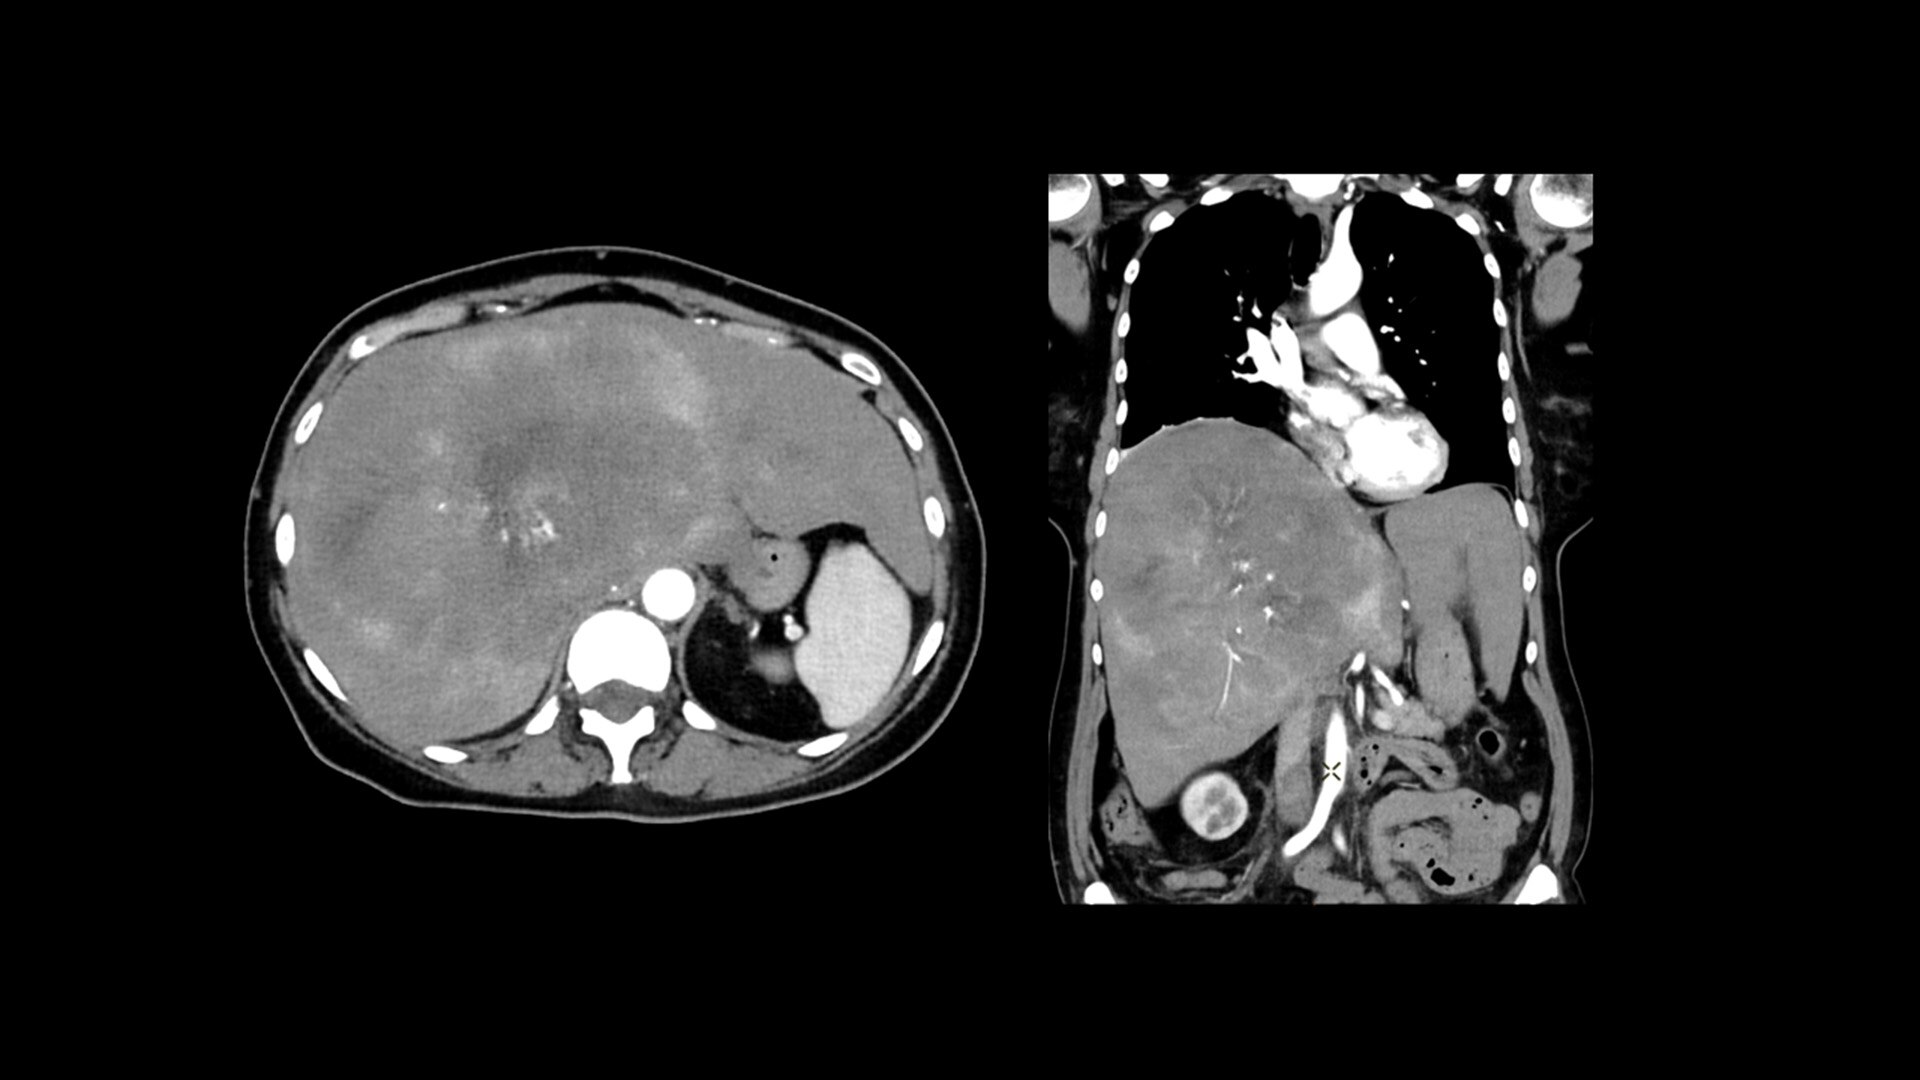

Cardiac CT has become a front-line, non-invasive imaging tool for diagnosing, treatment planning and monitoring of cardiovascular disease

Healthcare providers are striving to improve patient health but are struggling with increasingly complex exams, insufficient or inexperienced staff, and operational and capital efficiency. Revolution™ Vibe, designed to deliver leading-edge technology, features advanced cardiovascular capability. It improves patient access and operational efficiency, prioritizes patient care and supports your facility's growth with lower lifecycle costs.

Consistent, exceptional image quality for every patient

Unlimited 1-Beat Cardiac is designed to provide consistent, high-quality imaging for accurate diagnoses, even in challenging patients with atrial fibrillation, breath-holding difficulties, heavily calcified coronaries, in-stent restenosis, and situations where an ECG trace is unavailable.